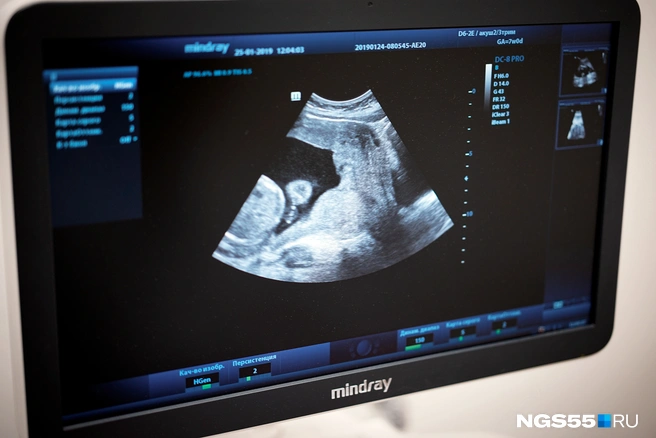

Один врач делал УЗИ, а репродуктолог проводил перенос. Прямо в матку поместили проводник, в него вставили шприц, где находился эмбрион. Это было быстро  — полторы-две минуты. И терпимо. Главное  — расслабиться, не напрягать тело, не зажиматься.

—  Я говорила себе, что осталось совсем чуть-чуть, просто перенести, расслабься, доверься врачу, себе, как-то отключись. Мне показали экранчик. Врач сказала: «Вот она, твоя звездочка». Я видела, как при нажатии шприца эмбрион переместился в полость матки. У меня даже фотография есть, врач прислала фото экрана. И всё. Я полежала, как доктор велела, и поехала домой,  — вспоминает Анна.